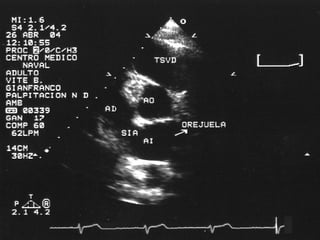

Eje Corto A nivel de la válvula aortica se puede observar:  Aorta, AI, AD, VD,  Válvula aórtica, con sus tres cúspides (derecha , izquierda y no coronariana), válvula pulmonar, válvula tricuspidea, septum IA, tronco de la arteria coronaria izquierda Permite identificar también el apéndice de la aurícula izquierda

Eje Corto Anivel de la válvula aortica se puede observar: Aorta, AI, AD, VD, Válvula aórtica, con sus tres cúspides (derecha , izquierda y no coronariana), válvula pulmonar, válvula tricuspidea, septum IA, tronco de la arteria coronaria izquierda Permite identificar también el apéndice de la aurícula izquierda